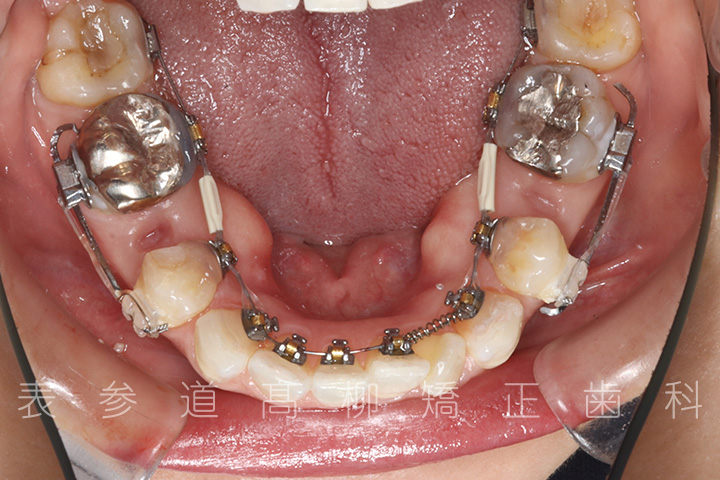

治療経過

• 治療開始

• 3ヶ月後

• 10ヶ月後

• 20ヶ月後

• 22ヶ月後

• 治療終了

・リンガルブラケット装置

・歯科矯正用アンカースクリュー(i-station)

・マウスピース型矯正装置